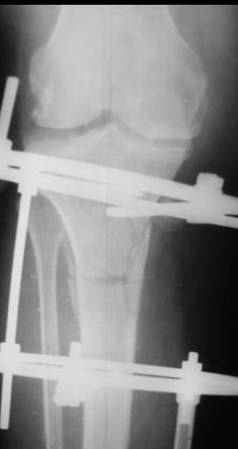

Глядя на снимки, кроме оперативного лечения в голову ничего не приходит. Хотя бы корригирующая кортикотомия б/б кости с минимальной внешней фиксацией. Высылаю пример.

На последнем фото внешний вид больной на завершающем этапе лечения (30 сутки) с трансформацией АВФ из гибридного в стержневой. Боль уходит сразу после операции. При данной Р-картине консервативно показано применение только обезболивающих препаратов - трамадол до 3 мес. по 100-200 мг в сутки, возможно внутрисуставное введение морфина 1,0 мл. При скрыто протекающем синовиите добавляются НПВС. Кроме того, должна помочь остеорефлексотерапия - в/костной иглой пункция проксимального метафиза б/б кости с введением 1,0-0,5 мл. физ.р-ра или новокаина. Возможе и вариант расширенного вмешательства по Беку: узким долотом через кожный разрез в 3-4 мм делается «прокол» кортикального слоя и маятникообразными движениями разрушается костный мозг. Боль проходит практически всегда и надолго.